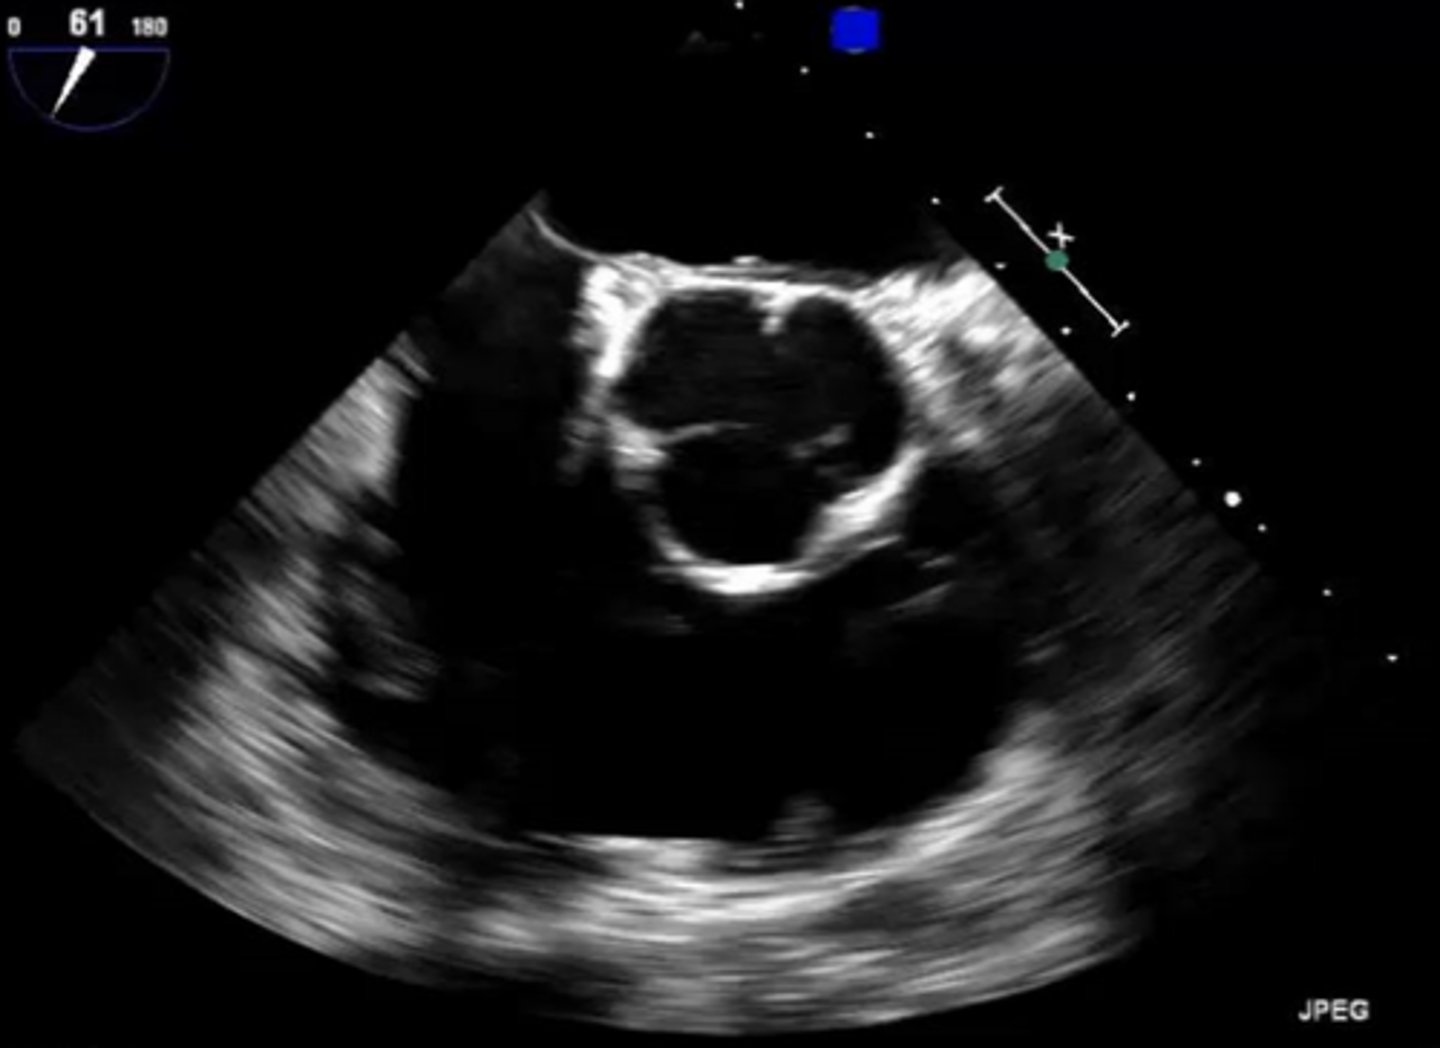

MV PLAX (top leaflet)

AMVL

MV PLAX (bottom leaflet)

PMVL